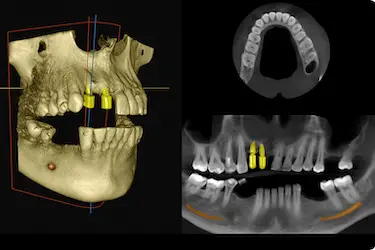

TAC para implantes dentales

Antes de proceder a la colocación de uno o varios implantes dentales, necesitaremos saber si tu mandíbula cuenta con la cantidad y densidad suficiente de hueso como para darle soporte. Esto es imposible de averiguar sin la realización de un TAC dental.

Además, el TAC para colocar un implante dental nos ayudará a saber el estado de las raíces dentales de tu boca y a determinar cuál es la posición exacta en la que debemos ponerlo.

En cirugías de regeneración del hueso

En caso de que el TAC dental nos confirme que el hueso no posee la calidad suficiente como para fijar los implantes, podremos planificar la técnica más adecuada para regenerarlo.

Por ejemplo, un injerto óseo que te ayude a recuperar la cantidad y densidad suficiente como para elevar lo máximo posible las probabilidades de éxito del tratamiento.

Esta prueba ayuda a prever la cantidad exacta de hueso necesaria antes de la cirugía.